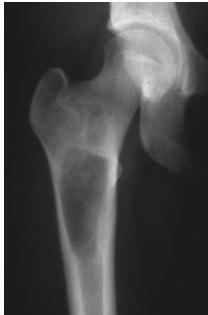

Clinical Example

- 11 year old boy: Pain in left hip

Osteoid Osteoma

- Small tumor (<1 cm)

- Young adults

- Pain, pain, pain:

- Typically relieved by Salicylates

- Sites: Femur, tibia, spine

- X-ray:

- Small radiolucent “nidus”

- Surrounded by sclerotic bone

- CT: Shows “nidus” better

- scan: hot

- Treatment: surgical excision, or thermal ablation

Source: Orthopedic Radiology. A Greenspan. Lippincott-Raven

Sources: Apley’s System of Orthop. And Fractures, http://openi.nlm.nih.gov/